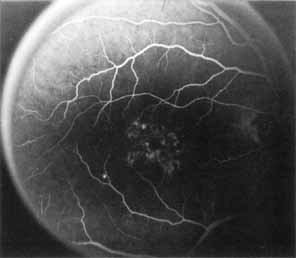

Although there is no reported genetic heterogeneity, there is wide phenotypic variation within the disorder. The major finding within the macula is a classic radial cystic maculopathy. Although retinal signs have been described in infants as young as 3 months, foveal schisis may be difficult to detect, leading to underdiagnosis. The diagnosis is usually not made until the affected male reaches school age (4 to 8 years of age) and encounters visual problems secondary to foveal involvement. Typical foveal schisis findings have been reported in 68% to 100% of eyes within various series.37,38 Foveal schisis is the only finding in about half the cases. It is characterized by the presence of radiate perifoveal microcysts located in the nerve fiber layer (Fig. 1) with radiate plications of the overlying internal limiting membrane that are seen especially well on monochromatic (red-free) photography (Fig. 2). The microcystoid change may slowly progress to form a macular cyst or hole. Foveal schisis has been reported in association with Goldmann-Favre vitreotapetoretinal dystrophy and rarely may be seen in rod-cone dystrophy or as an autosomal dominant or recessive condition.39–43